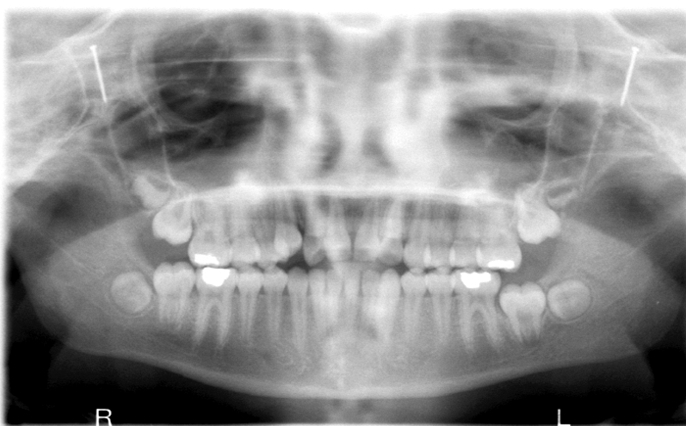

What is wrong with this image?

too far forward

double real image of cervical spine (superimposed on ramus)